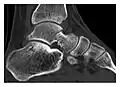

Fatigue fractures are more frequent in women which may be due to the relatively smaller bones of women. Moreover, pregnancy is a well-recognized risk factor for femoral neck fatigue fracture. While fibular and metatarsal fractures have a low risk of complications, other sites including the femoral neck, midanterior tibia, navicular, talar, and other intraarticular fractures are prone to complications such as delayed union, nonunion, and displacement. The site of the insufficiency fracture may be specific to the activity: for example, rugby and basketball players are more prone to navicular fractures, while gymnasts have a higher risk for talar fractures (Figure 7). Long distance runners are at increased risk for pelvic, tibial (Figures 8 and 9), and fibular fractures. In the military, calcaneus (Figure 10) and metatarsals are the most commonly cited injuries, especially in new recruits. Billiard players are at risk for upper limb fractures (Figure 11).[1]

a

b

Figure 7: Fatigue fracture of the talus in a 25-year-old male basketball player with right hind foot and ankle pain, without history of trauma, and a normal initial radiograph (not shown). (a) One-month followup lateral radiograph shows normal appearance. (b) Sagittal T1-weighted MRI shows an irregular fracture line (arrow) within an ill-defined area of hypointensity corresponding to bone marrow edema.[1]